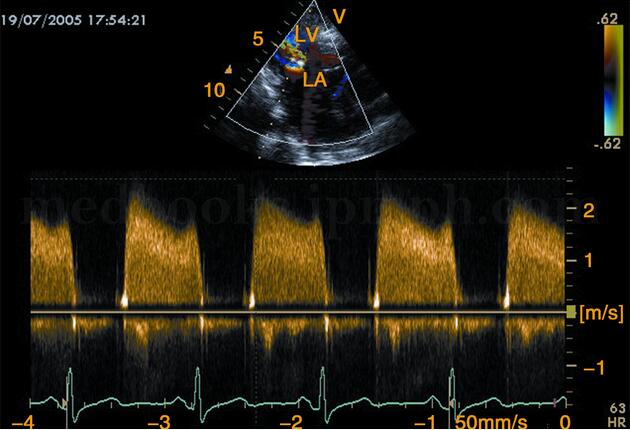

4﹒频谱多普勒超声 舒张期二尖瓣口血流速度增快,E‐A峰重叠,呈正向高速充填频谱(图2‐1‐124),峰值流速>1.5m/s。狭窄程度越重,峰值速度越快。

图2‐1‐124 脉冲多普勒显示舒张期二尖瓣狭窄射流频谱